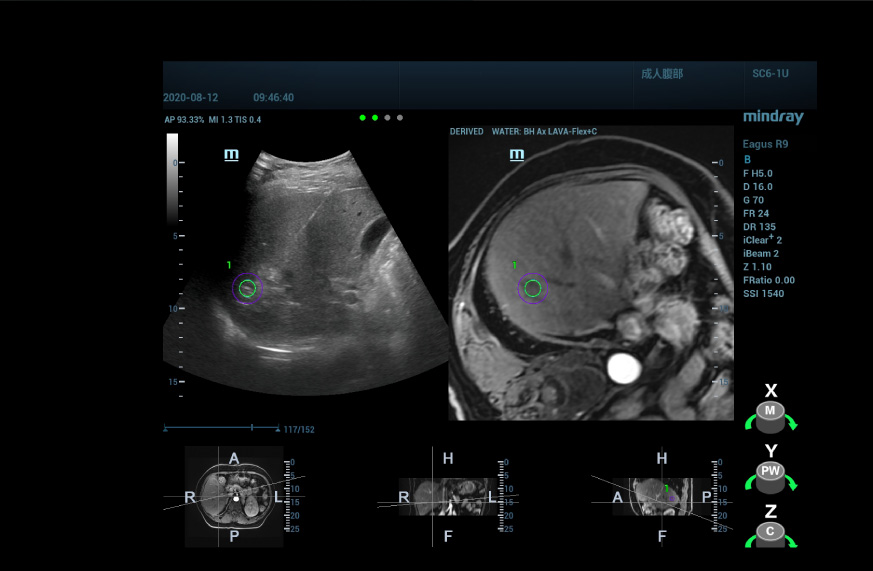

Mediante el empleo de una tĂ©cnica de fusiĂłn multimodal usando uHit Fusion de Mindray, se puede fusionar la informaciĂłn de la resonancia magnĂ©tica (MRI) con la imagen de la ecografĂa, lo que nos permite ver la ubicaciĂłn de los nĂłdulos anormalmente aumentados que se muestran en la mejora de la T1WI de la resonancia magnĂ©tica. Con la informaciĂłn de posicionamiento espacial adicional, ademĂĄs de la resonancia magnĂ©tica, podemos localizar la lesiĂłn con un alto grado de confianza.

En cuanto a la imagen de fusiĂłn de ecografĂa/ecografĂa, obtenemos datos de ecografĂa 3D de la lesiĂłn antes del procedimiento y los fusionamos con la imagen 2D en tiempo real para que la informaciĂłn de la evaluaciĂłn de la lesiĂłn previa al procedimiento se pueda utilizar por completo, y puedan confirmarse la ubicaciĂłn y naturaleza de la lesiĂłn realizando una ultrasonografĂa de nuevo.

Para los movimientos respiratorios inevitables y los movimientos corporales imprevistos durante el tratamiento, introdujimos funciones de correcciĂłn de movimiento y compensaciĂłn respiratoria para corregir los cambios de posiciĂłn durante la fusiĂłn y hacer que el registro de la ablaciĂłn sea mĂĄs preciso y estable.